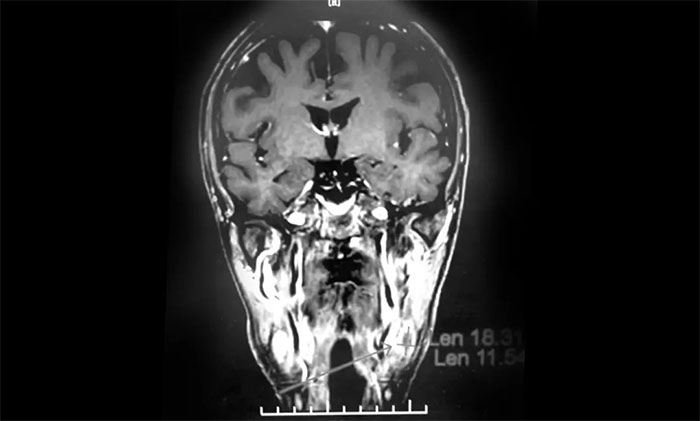

經(jīng)MDT多學(xué)科會診評估,制定以放療為主的同步放化療方案。治療后復(fù)查MRI,患者左側(cè)鼻咽部實(shí)性占位較前治療明顯減小;原左側(cè)下頜腺區(qū)、咽旁腫大淋巴結(jié)已基本吸收好轉(zhuǎn),左頸部腫大淋巴結(jié)較前明顯縮小。

▲ 放療后復(fù)查MRI,腫瘤占位較前明顯減小